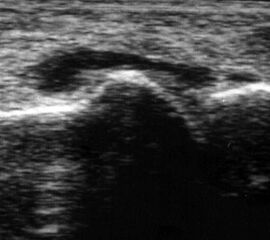

Hämarthros mit Binnenechos

Abbildung 6

Lagerung: Rückenlage.

Schnittebene: Ventraler LS über dem OSG.

Referenzstrukturen: Distale Tibia und Talusrolle, darüber Gelenkkapsel. Befunde: Echoarme Vorwölbung der Gelenkkapsel durch Hämarthros (Abb.6), gelegentlich Spiegelbildung durch Abscheidung von flüssigen und korpuskulären Anteilen. Nach dem zweiten Tag zunehmend echogener und teilweise mit fokalen Verdichtungen durch Thrombosierung. Dekompressionstest zur Abklärung der Punktionsfähigkeit.